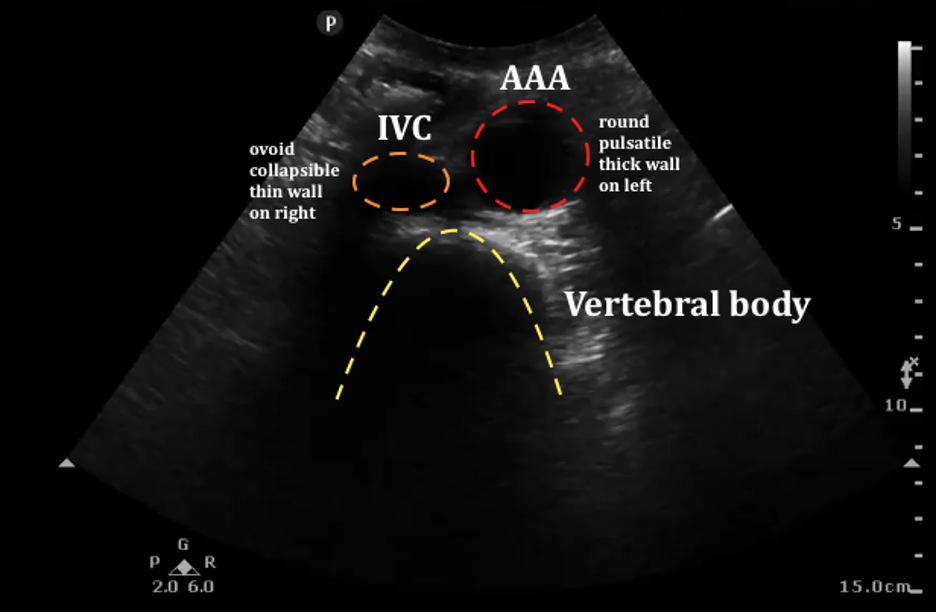

Abdominal Aortic Aneurysm

Abdominal aortic aneurysm (AAA) is a relatively common finding in patients over 50 years of age, especially with smoking history, and can be evaluated using emergency ultrasound. Dilation of the abdominal aorta greater than 3 cm indicates AAA and patients with dilation greater than 5 cm (Figure 23) are at increased risk for spontaneous rupture of the aorta (REF. 9). In patients with symptoms concerning for ruptured AAA, clinician-performed ultrasound can speed diagnosis and treatment in this life-threatening condition.

Figure 23. Upper image with normal abdominal aorta localized anterior to the spine (arrow), bottom image with large AAA. Upper image Courtesy of emDocs and is used under the Creative Commons Attribution 4.0 International License. The original image is located at: emDOCs.net – Emergency Medicine EducationUS Probe: Ultrasound for Abdominal Aortic Aneurysm - emDOCs.net - Emergency Medicine Education. The lower image is courtesy of Taming the SRU and used under the Creative Commons Attribution-NonCommercial-ShareAlike 4.0 International License. The original image is located at: US - Abdominal Aortic Aneurysm - Ultrasound Case of the Month — Taming the SRU.